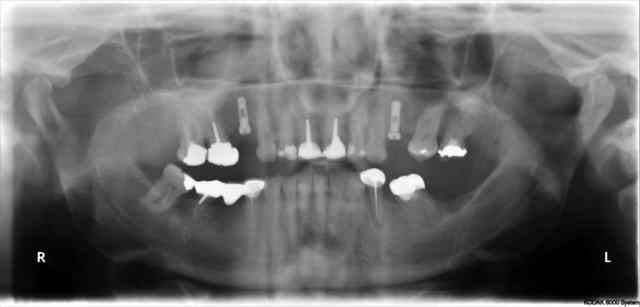

???? tu as un pano ou un scan je ne situe pas ça comme une cloison, mais je vois mal.

sinon félicitations pour ton premier sinus lift... ;-))

j'ai la pano au cab...pas de problème...çà peut aussi être un épaississement de la membrane dans ce cloisonnement...il a eu un bon rhume quelques semaines avant...